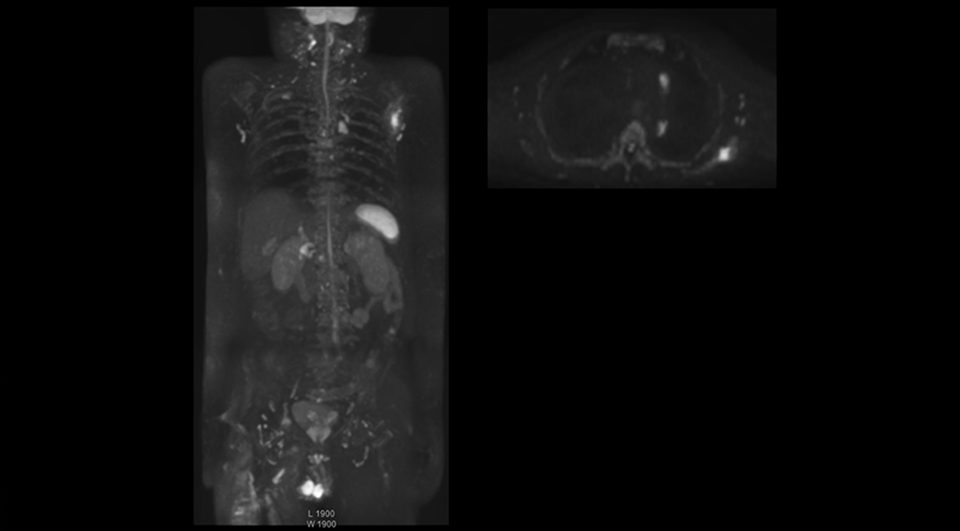

“The DWIBS sequence’s value in oncology cases is due to the high contrast it creates between lesions and surrounding tissue. Whole body DWI is requested by physicians who need to clarify TNM staging or determine therapeutic strategies, oncologists in need of diagnosis or follow-up scans, surgeons who need to see the presence of distant lesions that are sometimes difficult to detect by CT before surgery, and urologists for the evaluation of bone lesions, and the effect of chemotherapy and radiotherapy.”

After implementing the improved whole body protocol, the radiology team initially did not see a large increase in referrals, although Dr. Nobusawa saw clinical cases where the DWIBS images provided him valuable information for diagnosis. This is why Dr. Nobusawa and Mr. Naka started to actively educate referring physicians about the value of whole body DWIBS. They organized several presentations for physicians in the hospital, where they explained how DWIBS can be of value in oncology patients. The information it provides can be useful for physicians when staging cancer, as well as when determining or adjusting treatment strategy. Mr. Naka remembers some cases where DWIBS provided remarkable information. “In one example, DWIBS visualized bone lesions that could not be seen on PET or SPECT. In another case we had found a bone lesion when a normal L-spine scan for narrowing of the disk space was done. One extra DWIBS scan (2 stations, 8 minutes) demonstrated a lesion that later was confirmed to be the primary region of cancer.”

In certain cases, radiologists now choose DWIBS to make diagnoses that used to depend on nuclear medicine studies. “We don’t have SPECT or PET in our hospital, so for instance for visualizing metastasis and monitoring the effect of treatments such as chemotherapy or radiotherapy, we used to refer patients outside the hospital. Now, these patients are sent to MRI for our whole body protocol with DWIBS,” Mr. Naka says.